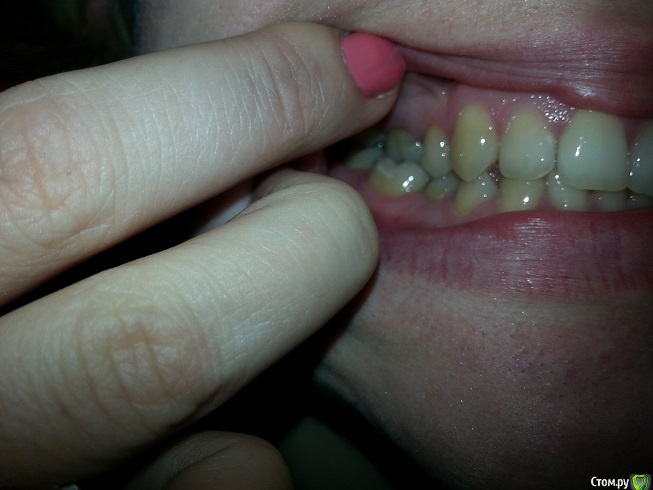

zimazima Опубликовано 20 ноября, 2015 Поделиться Опубликовано 20 ноября, 2015 Добрый вечер!Опытные ортодонты, скажите, пожалуйста, будет ли необходимо в моем случае удалять нижние 4ки? Какова вероятность того что НЧ выйдет вперед после ношения брекетов? предыстория: в 17 лет носила брекеты на ВЧ, т.к. слева клык рос поверх ряда удалили 4ку и поставили на ее место клык...при этом ВЧ потеряла симметрию((и кажется что проявилось это спустя годы (сейчас мне 30). и теперь за счет того что НЧ не ровнялась зубы начали разворачиваться опять... вопросы:- какова вероятность того что удаление нижних 4к не потребуется при лечении?(ортодонт говорит что можно поносить пол года и посмотреть в процессе, имеет ли это смысл? или лучше не терять время, может все очевидно?...)- можно ли оставлять 8ки?- реально ли вернуть центр ВЧ на место если удалить 4ку слева?- при удалении нижних и верхних 4к как сильно сузится лицо и подбородок станет ли еще более выпирающим? (лицо у меня и без того узкое и длинное, достаточно большой нос картошкой и выступающий подбородок) не станет ли хуже?- не будет ли после лечения других проблем с искривлением лица (оно у меня сейчас не симметричное - глаза на разном уровне))), на фото вижу особенно это(( в общем в жизни не так вроде бы все и плохо выглядит - на фото просто кошмар - сама посмотрела и уже готова на все.волнуюсь не будет ли хуже в моем случае? очень благодарна за любые ответы - советы - комментарии! спасибо!выложу доп фото по запросу любые нужныеЗлобина А.В. Заключение.pdf Ссылка на комментарий